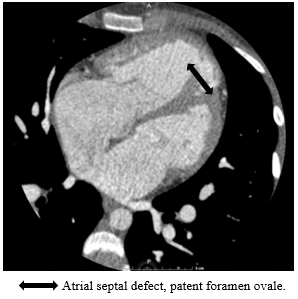

Upon regaining alertness, the patient comments that a study was carried out that has not been assessed by the treating physician: Contrasted cardiac tomography on 05/19/21 with a report of: atrial septal defect, patent foramen ovale 9 x 7 mm, interatrial septum defect 28x 25x 29 mm, pulmonary artery with a dilated appearance and a caliber of 44 mm, coronary arteries with little value due to movement and lack of dilation, secondary increase in lung vascularity (Figure 3).

Figure 3 Tomographic image showing atrial septal defect.